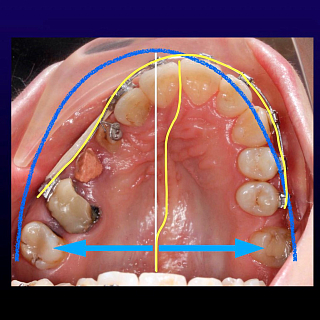

4. Ошибки и осложнения при коррекции асимметричных состояний. Коррекция дентальных асимметрий. Закрывать или открывать дентальные промежутки при первичной или вторичной адентии? Соблюдение периметра зубного ряда как залог успешного ортодонтического лечения.